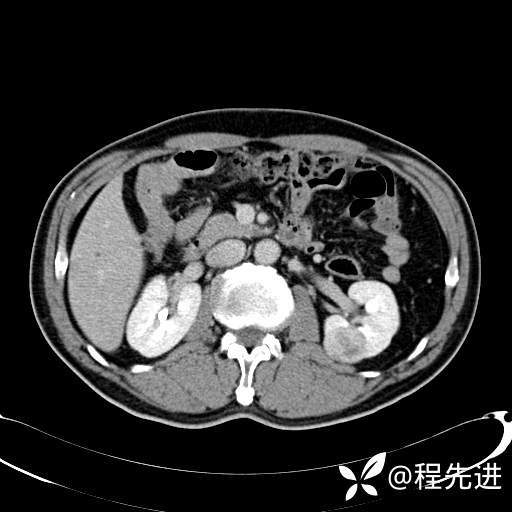

患者性别:男

患者年龄:65岁

简要病史:腰痛2月,体检发现左肾占位5天

皮质期: